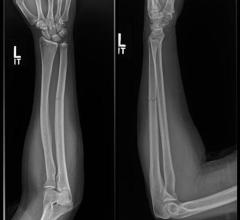

August 5, 2022 — GE Healthcare released its most advanced fixed X-ray system yet, the next-generation Definium 656 HD ...